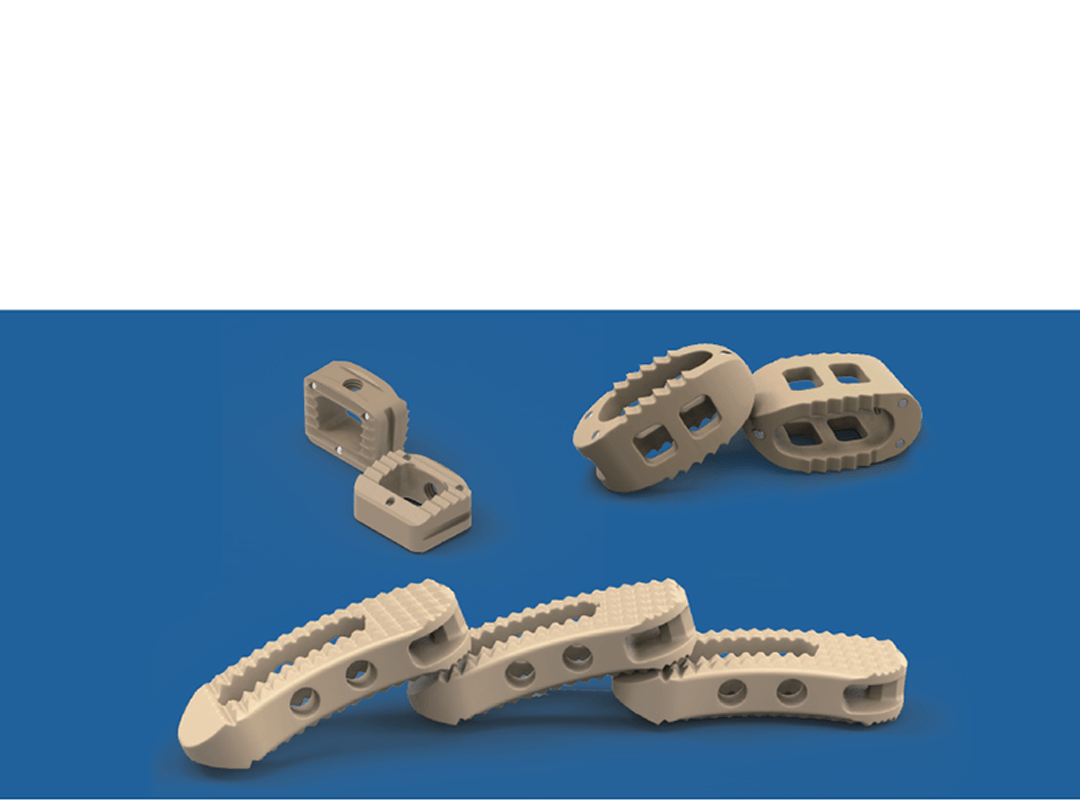

Coales Interbody Fusion Cage System

Cages anatômicos em PEEK para fusão intersomática espinhal.

Sistema de cages para fusão intersomática, com diferentes modelos (Coales-P, C, M, T, L e Mesh), em PEEK, com marcadores de tântalo para melhor visualização e adesão óssea.

Apresentação:

- Materiais: PEEK (ASTM F2026), Tântalo.

- Medidas: Diversas opções de altura, largura e ângulo de lordose.

- Usos principais: Fusão espinhal lombar e cervical, oferecendo estabilidade e suporte biomecânico.

Recomendações:

- Tipo de produto: Cages intersomáticos para coluna vertebral.

- Compatibilidade: Compatível com técnicas de fusão TLIF, PLIF, ACIF, etc.

- PH: Neutro (inerte ao corpo humano)

Importante:

Design anatômico • Radiotransparente • Marcadores de tântalo para visualização • Reduz risco de subsistência